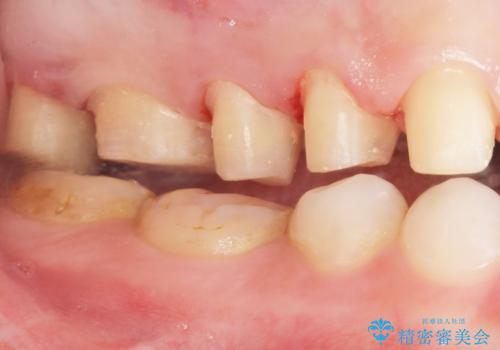

矯正を途中でやめてしまったとのことで、歯に矯正の接着材が残っており着色も顕著でした。

奥歯の咬合面にはレジンが盛られた状態でした。

見た目と咬み合わせを改善するため、セラミッククラウンによる治療を行いました。